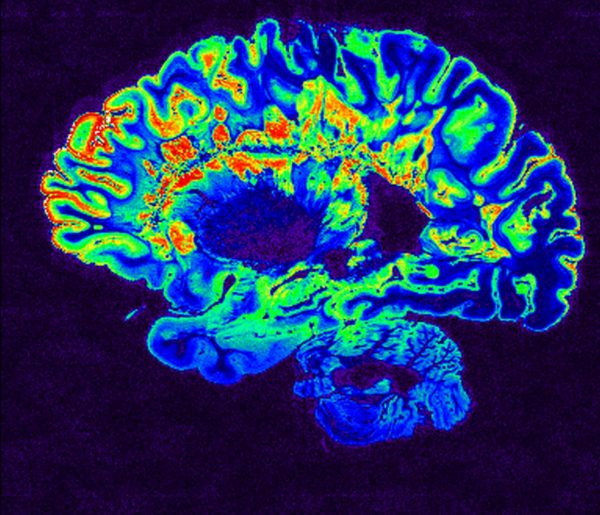

Η πολλαπλή σκλήρυνση οδηγεί σε απομυελίνωση των νευρικών κυττάρων – κοινώς φθείρει την προστατευτική μόνωση γύρω από τους νευρώνες που ονομάζεται μυελίνη αφήνοντας τους νευράξονες οι οποίοι μεταφέρουν τα ηλεκτρικά σήματα εκτεθειμένους, όπως τα γυμνά καλώδια. Η διαδικασία αυτή οδηγεί σε σοβαρά προβλήματα κίνησης, ισορροπίας αλλά και όρασης και χωρίς θεραπεία οι α

σθενείς μπορούν να καταλήξουν παράλυτοι και με μικρότερο προσδόκιμο ζωής.

H πολλαπλή σκλήρυνση προκακαλεί καταστροφή της μυελίνης, της «μόνωσης» που προστατεύει τα νευρικά κύτταρα (NIH)